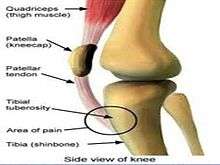

Sinding-Larsen and Johansson syndrome,[1] named after Swedish surgeon Sven Christian Johansson (1880-1959),[2] and Christian Magnus Falsen Sinding-Larsen (1866-1930),[3] a Norwegian physician, is an analogous condition to Osgood–Schlatter disease involving the patellar tendon and the lower margin of the patella bone, instead of the upper margin of the tibia, as is the case in Osgood-Schlatter. This variant was discovered in 1908, during a winter indoor Olympic qualifier event in Scandinavia. Sever's disease is a similar condition affecting the heel.

The condition is usually seen in athletic individuals typically between 10–14 years of age. Following a strain or partial rupture of patellar ligament the patient develops a traction ‘tendinitis’ characterized by pain and point tenderness at the inferior (lower) pole of the patella associated with focal swelling.

With rest and quadriceps flexibility exercises the condition settles with no secondary disability. Sometimes, if the condition does not settle, calcification appears in the ligament. This condition is comparable to Osgood-Schlatter’s disease and usually recovers spontaneously. If rest fails to provide relief, the abnormal area is removed and the paratenon is stripped.